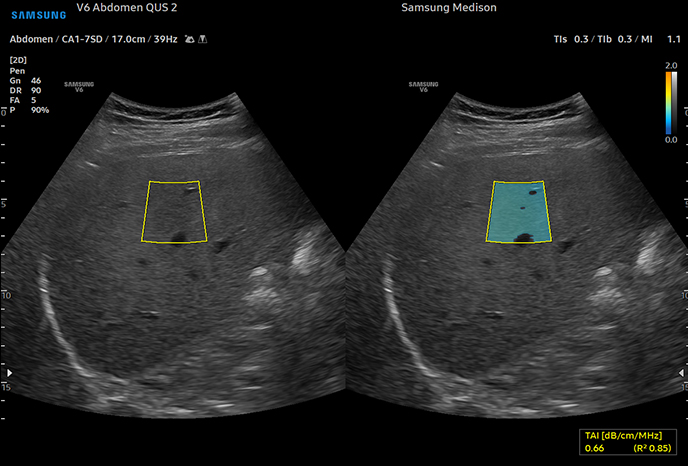

하이앤드 초음파 장비를

활용한 정밀 심장 검사

심장 질환 진단에서 가장 중요한 것은 ‘심장의 상태를 얼마나 정확하게 볼 수 있느냐’입니다. 저희 센터는 대학병원급 하이앤드 초음파 장비를 도입하여, 실시간 3D 렌더링으로 정밀 진단이 가능하며, 심장의 구조·혈류·기능을 실시간 고해상도로 관찰합니다.

미세한 판막 움직임, 혈류 속도 변화, 심방·심실 크기와 수축력까지 정밀하게 분석할 수 있어, 심장질환의 조기 발견과 치료 계획 수립에 큰 차이를 만듭니다.